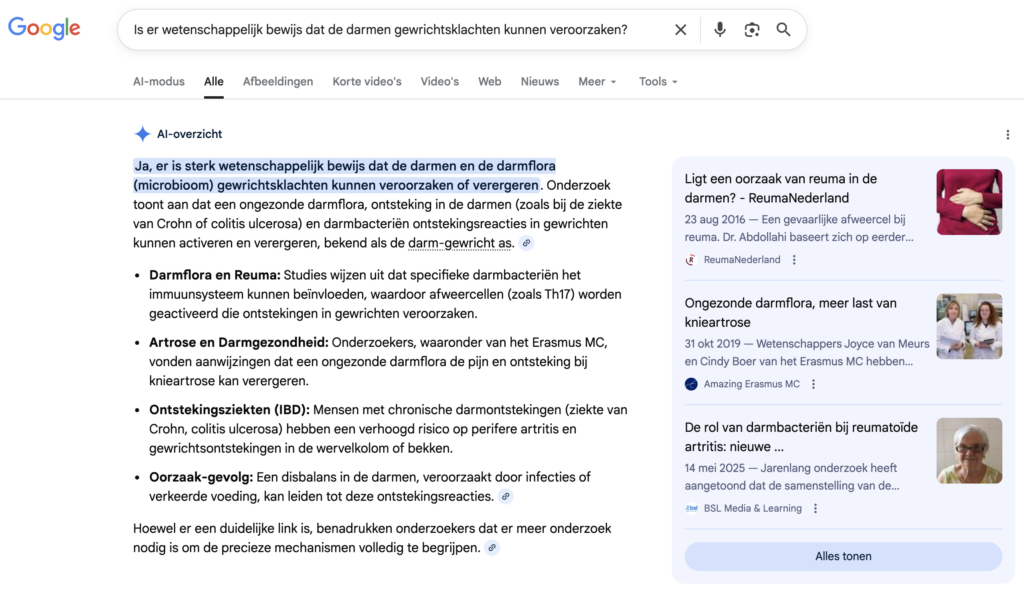

Ik begon met een eenvoudige vraag in de zoekbalk van Google:

Het antwoord: Ja, en heel veel.

Ik kwam tientallen onderzoeken tegen van de afgelopen jaren – van gerenommeerde instituten zoals Stanford University, de Mayo Clinic en Shanxi Medical University in China.

En ze kwamen allemaal tot dezelfde conclusie:

Mensen met chronische gewrichtsproblemen hebben een aantoonbaar verstoorde darmflora.

Een meta-analyse door de Shanxi Medische Universiteit die 18 internationale onderzoeken analyseerde, toonde aan dat

- Patiënten met inflammatoire gewrichtsaandoeningen hebben significant minder diverse en minder gunstige darmbacteriën in vergelijking met gezonde mensen.

- Hoe verstoorder de darmflora, hoe sterker de ontstekingsreactie in de gewrichten.

Een onderzoek door de Stanford Universiteit ging zelfs nog verder:

Ze kon bewijzen dat bepaalde bacteriestammen in de darm direct verband houden met de ernst van gewrichtsontsteking.

En onderzoekers van de Mayo Kliniek ontdekten:

Mensen met leaky gut syndroom (doorlaatbare darmbarrière) hebben een aanzienlijk verhoogd risico op inflammatoire gewrichtsaandoeningen.